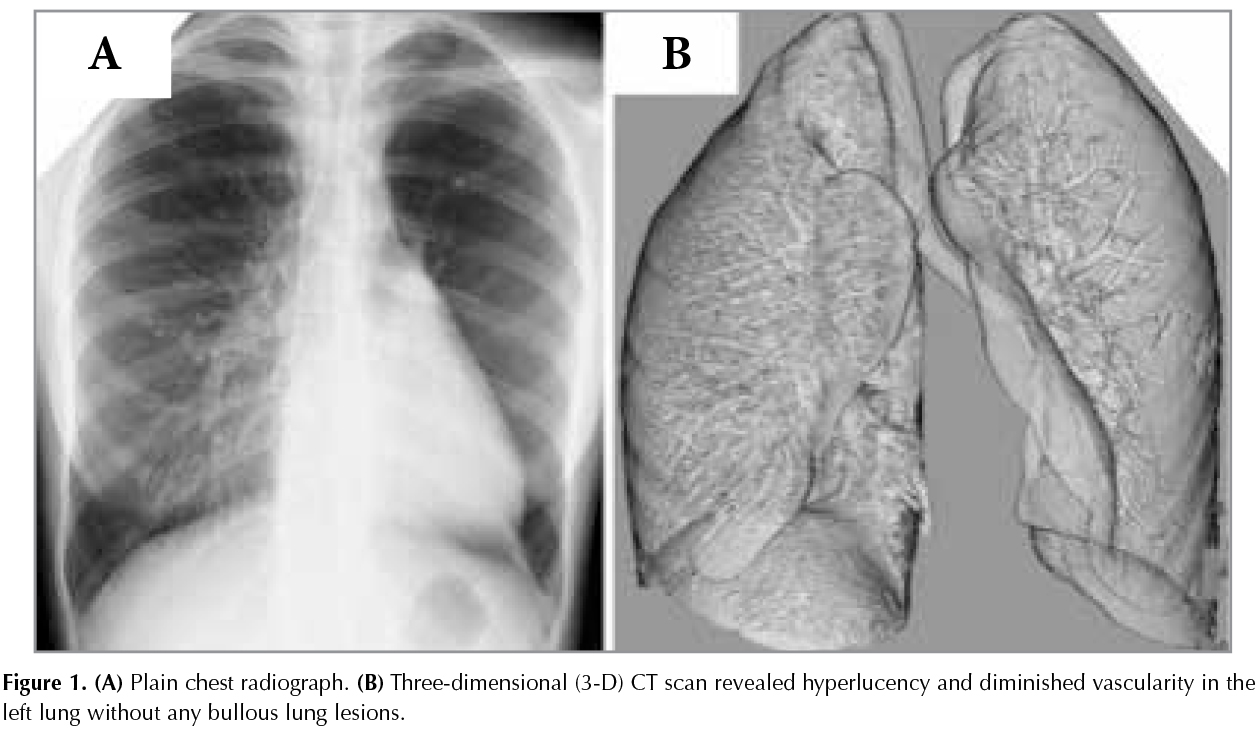

A 16-year-old woman was referred due to a left hyperlucent lung, which was incidentally observed on a chest radiograph (Figure 1A).The patient had a history of respiratory infection in her infancy. A three-dimensional (3-D) CT scan revealed hyperlucency and diminished vascularity in the left lung without any bullous lunglesions (Figure 1B). On the basis of these findings, the patient was diagnosed to have Swyer-James syndrome (1,2).When unilateral hyperlucent lung is discovered, a 3-D CT scan would provideimportant clinical information as observed in this case. Although extremely rare, Swyer-James syndrome should be included in the differential diagnosis of unilateral hyperlucent lungif patients have a history of pulmonary infection in their early childhood.

Figure 1A,B